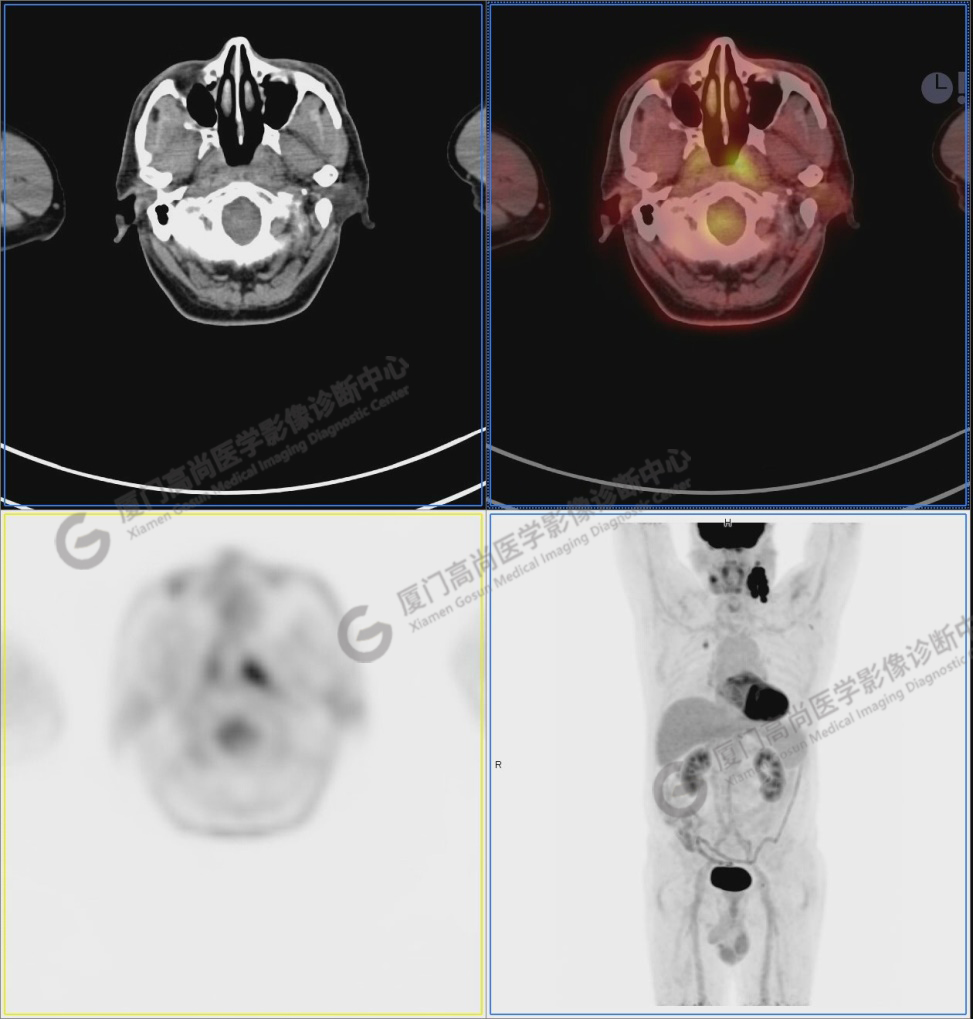

圖2:雙側(cè)頸部多發(fā)增大淋巴結(jié),代謝不同程度增高,考慮為轉(zhuǎn)移。

圖6-9:鼻咽左側(cè)壁增厚,代謝異常增高,考慮為鼻咽癌